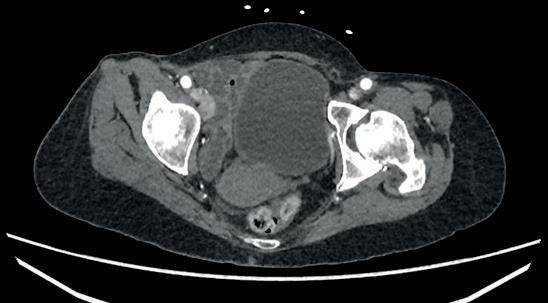

Left: Pre- and postoperative images (courtesy of Dittmar Böckler) of the first European implantation of the Gore Tag TBE; above: Dittmar Böckler performing the implantation